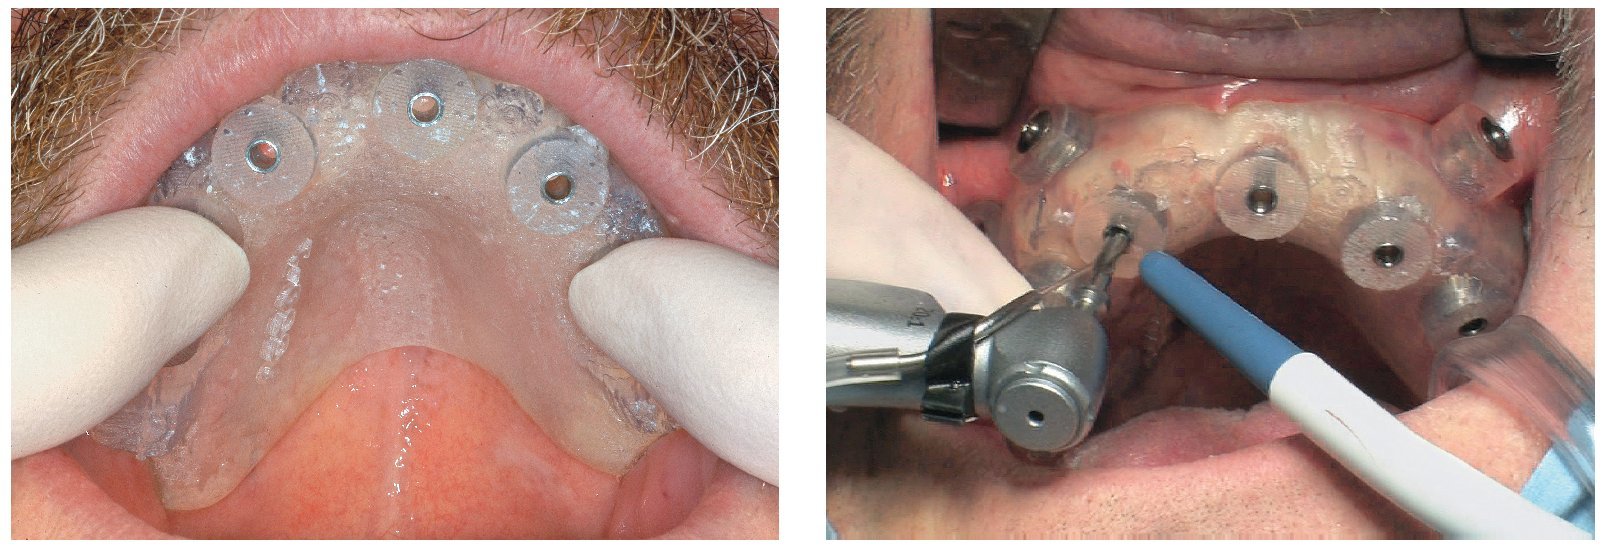

Fig. 65. Los implantes en el maxilar superior, integrados mediante técnica sin colgajo, y los pilares correspondientes para prótesis atornilladas.

La intervención quirúrgica (figs. 63 y 64) se realizó bajo anestesia local y se trataron al mismo tiempo ambas arcadas dentarias. Durante la primera fase se insertaron seis implantes cónico-cilíndricos (SPI®CONTACT, Thommen Medical AG, Waldenburg, Suiza) en la arcada dentaria superior mediante un acceso sin colgajo. Para ello se utilizaron los pilares pertinentes para reposiciones de puente atornilladas oclusalmente (VarioMulti, Thommen Medical AG, Waldenburg, Suiza) (fig. 65). Tras la intervención quirúrgica se colocó en boca la prótesis provisional prefabricada a partir de los datos de planificación y tallada en las posiciones de implante y se unió a las cofias provisionales (fig. 66 y 67); para ello se utilizó un composite de fraguado dual. Mediante una prótesis provisional mucosoportada se pudo preservar la estructura gingival hasta el momento de la implantación, y con ello la relación correcta entre los maxilares superior e inferior. Para la arcada dentaria inferior se utilizaron implantes cilíndricos (Element, Thommen Medical AG) (figs. 68 y 69). En combinación con los pilares pertinentes para prótesis atornilladas, se procedió aquí de la misma manera que en el maxilar superior. Una vez se hubo alineado oclusalmente la prótesis provisional del maxilar inferior con respecto al superior, se fijó sobre las cofias provisionales (fig. 70); debido a la formación de colgajo no había sido posible la alineación sobre la mucosa. Este procedimiento permite preservar la dimensión oclusal vertical que se definió al principio del tratamiento. A continuación se repasan, se pulen y se envían a la clínica para su incorporación las prótesis provisionales, las cuales, por el contrario, se apoyan exclusivamente sobre los implantes (figs. 71 y 72). Allí tienen lugar el control radiológico y el rectificado oclusal (figs. 73 y 74).